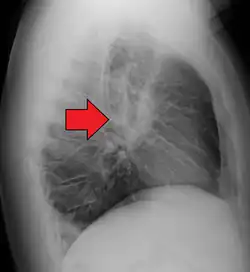

-

Hilar adenopathy especially on the person's left (coronal CT) -